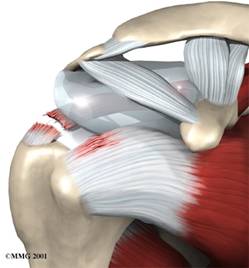

Einklemmen (Impingement) mit Reizung des Schleimbeutels (Bursa) beim seitlichen Anheben des Armes

Druckschmerzen im Bereich der Supraspinatussehne sind dabei in beiden Fällen typisch. Dabei können die Schmerzen über den Oberarm hinweg bis in die Hand ausstrahlen. Häufig findet man zeitgleich ein Einklemmungssyndrom, ein sogenanntes Impingement – Syndrom bedingt durch eine Engpasssymptomatik im Bereiche des Schultereckgelenkes, die verschiedene Ursachen haben kann (Schleimbeutelreizung, Arthrose des Acromioclaviculargelenkes, stark bogenförmiges Acromion (Teil des Schulterblattes)).